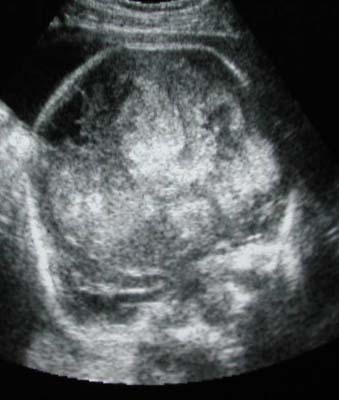

Tumeur astrocytaire maligne